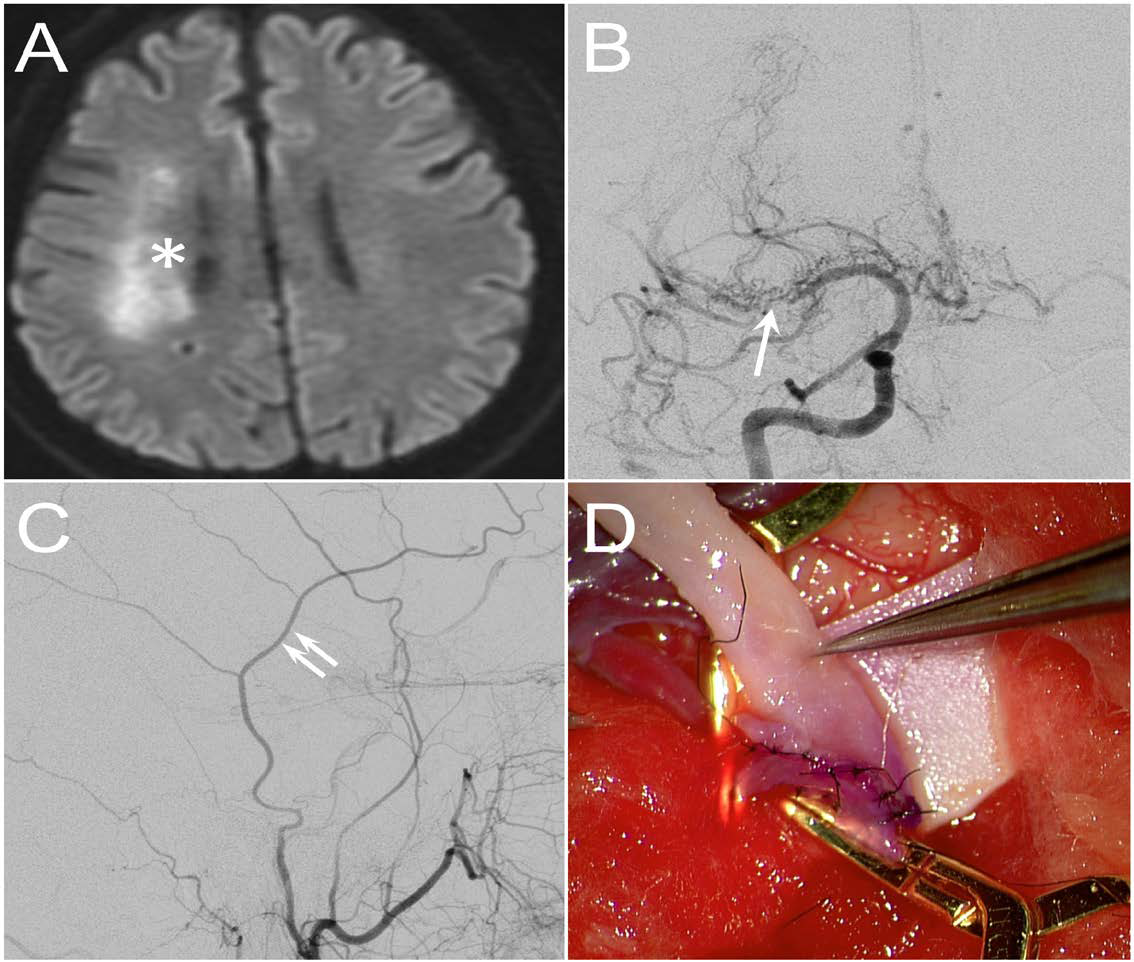

Figure 1: (A) DWI protocol of brain MRI showed multiple border zone infarcts at the centrum semiovale of the right hemisphere (star sign). (B) Frontal view of right internal carotid artery (ICA) angiogram revealed that the stenotic part of the right MCA was characterized by a network of fine but tortuous arterial twigs (arrow). (C) The frontal branch of the STA (double arrows) was selected as the donor artery. (D) Intraoperative photo showed the completion of STA-MCA end-to-side anastomosis.